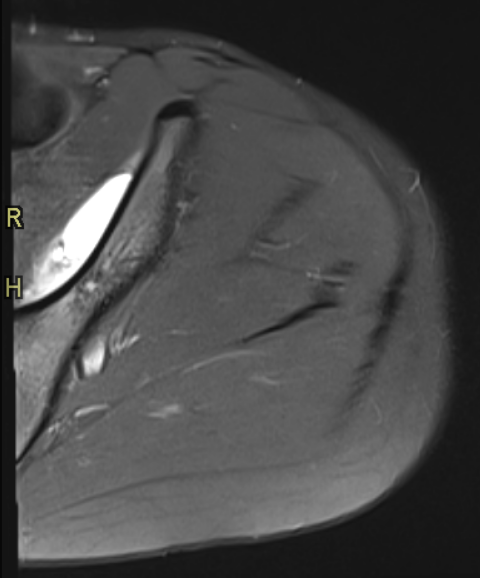

RM de cadera izquierda, secuencia PD TSE FS axial (Imagen 1) y sagital (Imagen 2). Se observa una imagen lentiforme subperióstica ilíaca de alta señal, bien delimitada, con un nivel líquido-líquido.